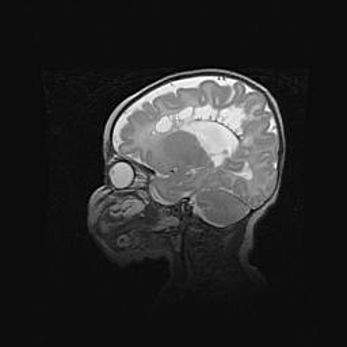

Множественные кисты обоих полушарий головного мозга, наибольшая из них в правой затылочной области. Ассиметричная атрофическая гидроцефалия.

Возраст: 7 месяцев

Вес: 5660 г

Пол: мужской

Окружность головы: 41,5 см

Срок гестации: 28-29 недель

Кисты головного мозга развиваются в результате многоочаговых некрозов вещества мозга и возникают вследствие перенесенной перинатальной инфекции, менингитов, энцефалитов, асфиксии, родовой травмы, расстройств мозгового кровообращения различного генеза. Образованию кист в веществе головного мозга плодов и новорожденных способствуют такие факторы, как высокое содержание в нем воды, недостаточная (или отсутствие) миелинизация и слабая астроглиальная реакция на повреждение.

Кисты могут сочетаться с гидроцефалией и другими поражениями головного мозга.